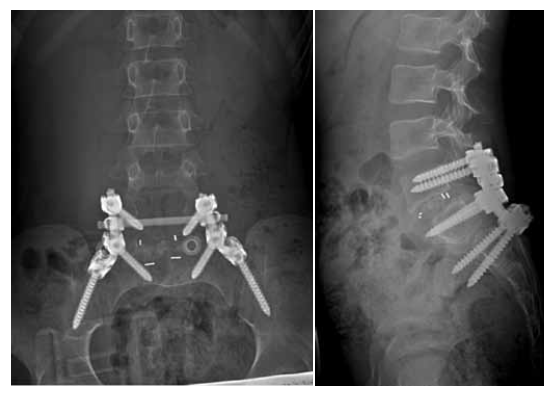

According to the radiological data of the lumbar spine, spondylolisthesis of degree 2 L5 was detected (Fig. 1). As observed on the MSCT of the lumbar spine (see Fig. 1), there was a congenital malformation, a bilateral slit-like bone defect in the inter-articular part of the L5 arch. Spina bifida posterior of L5. True spondylolisthesis of L5 of the degree 2. Deformity of the intervertebral disk L5–S1 and the cranial part of the body S1.

Fig. 1. MSCT of the lumbar spine before surgery

After clinical, neurological, and instrumental examinations, diagnoses of dysplastic spondylolisthesis of L5 of degree 2 (44%), bilateral foraminal stenosis of L5–S1, segmental instability of L5–S1, bilateral dynamic compression syndrome of L5 roots, and lumbodynia syndrome were established.